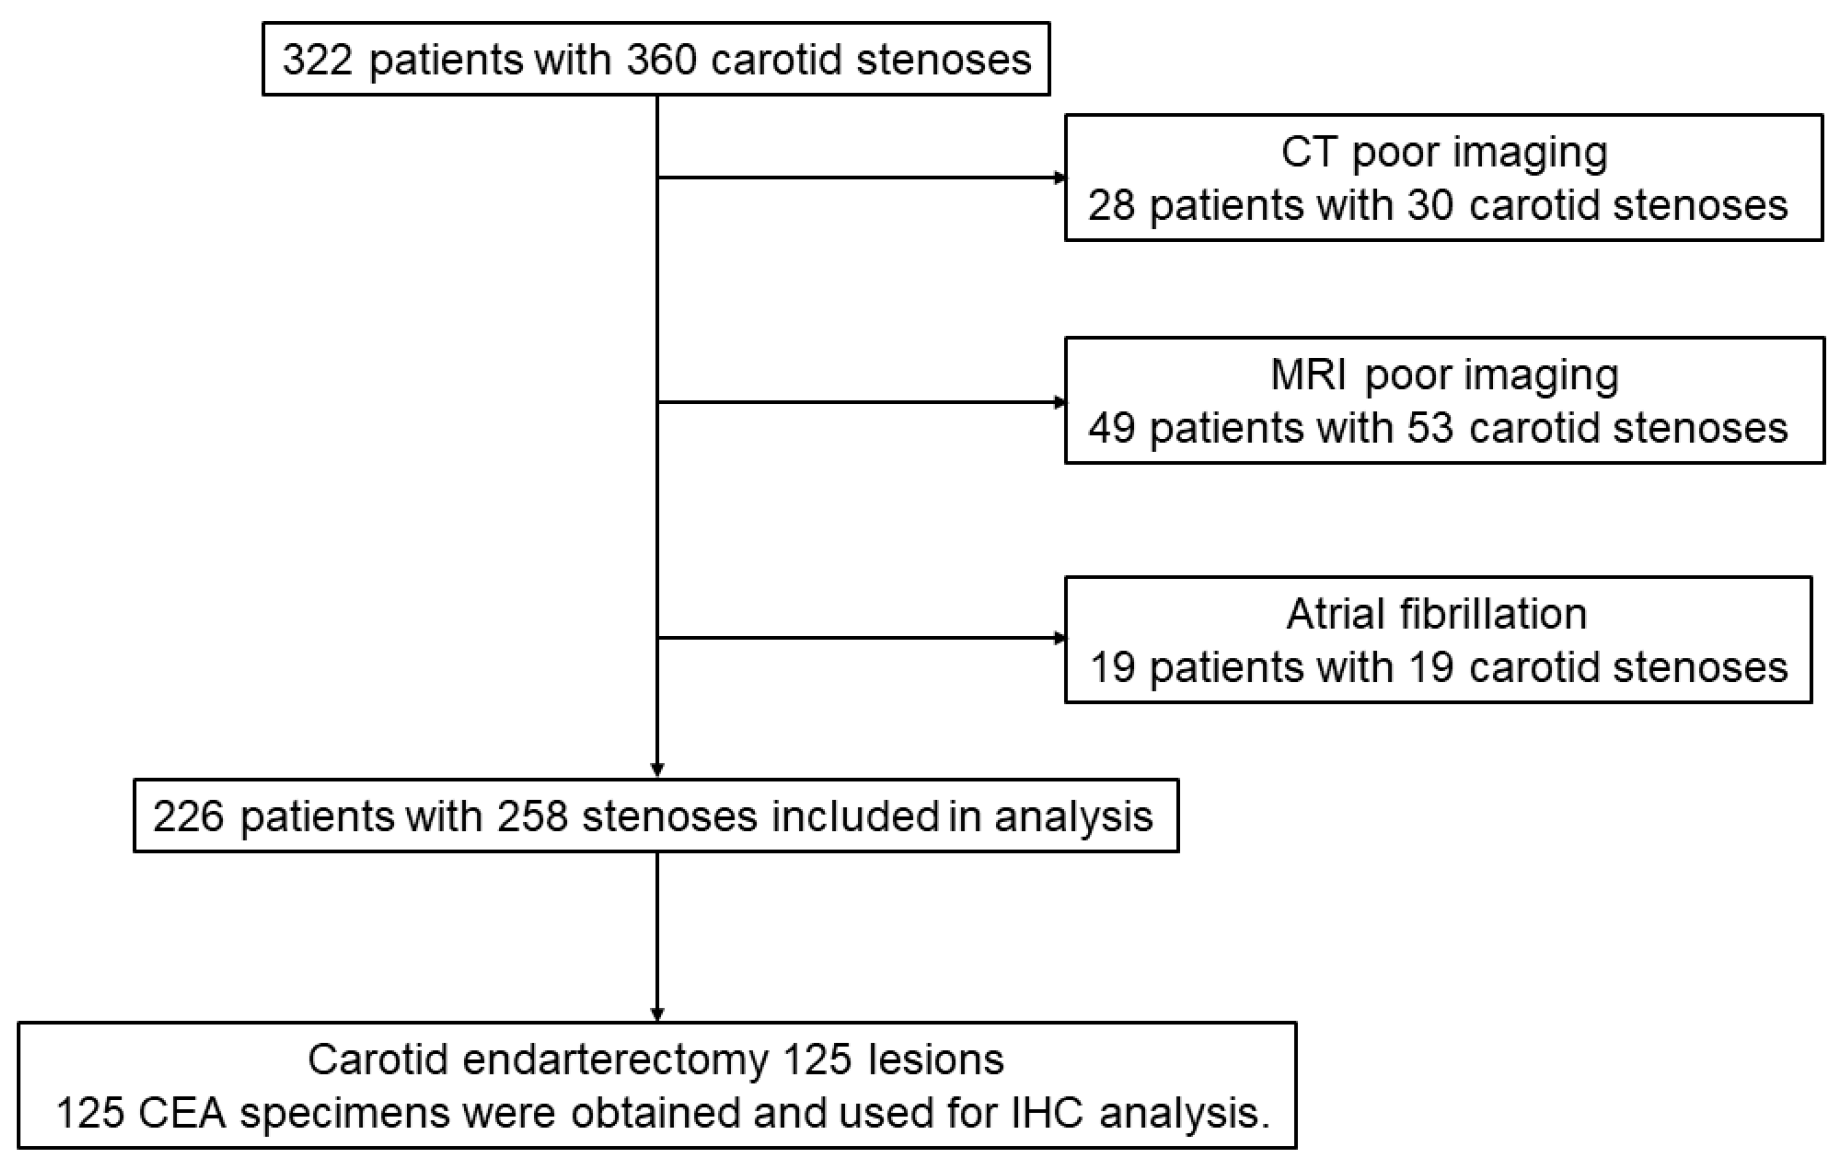

2.2. Study Population